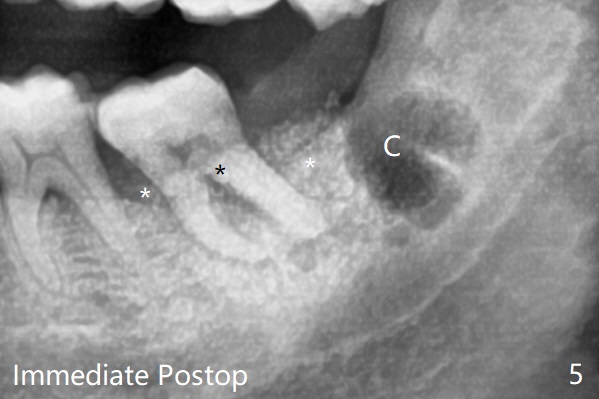

65岁女,南方人(广州),主诉左下肿胀,8舌侧粘膜穿孔(图一(舌侧观):<),初步问诊,回答:“全身没问题”,详细问诊:骨质疏松,静脉注射Reclast两年,准备拔除使用PRF修复缺损,全景片显示7远中骨质吸收严重(图二),因此8拔出后,牙槽窝塞入胶原塞(图五:C),将粘性骨粉放置7近中,远中(图五:白*)以及颊侧(黑*),把一片PRF膜覆盖骨粉(7颊侧,8牙槽窝口),另外一片放置于8舌侧穿孔(图四:箭头)颊侧,促进愈合,然后使用4-0 PGA缝合(图三(颊侧观),图四(舌侧观))。术后5天用钢丝(图六:*)和树脂固定松动牙,并且降低咬合。舌侧穿孔正在愈合(图七:>)。虽然术后三周智齿伤口裂开,但是没有症状,病人满意第二磨牙不再松动(图八),开始深洗。下次复诊拍摄根尖片观察骨质愈合。术后二个月第二磨牙远中没有骨质再生(图九),临床上远中牙根暴露。